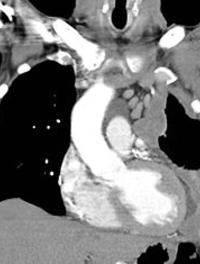

L’hypertension artérielle pulmonaire (HTAP) chronique d’origine thromboembolique est caractérisée par l’obstruction des vaisseaux pulmonaires [...]